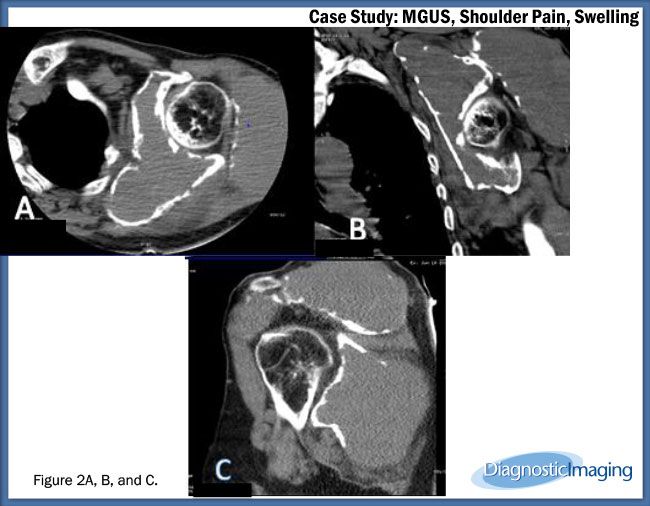

Case History: 62-year-old male with proven case of monoclonal gammopathy of unknown significance with shoulder swelling, pain.

Case History: A 62-year-old male with proven case of monoclonal gammopathy of unknown significance presented with complaint of left shoulder swelling and pain for three months.